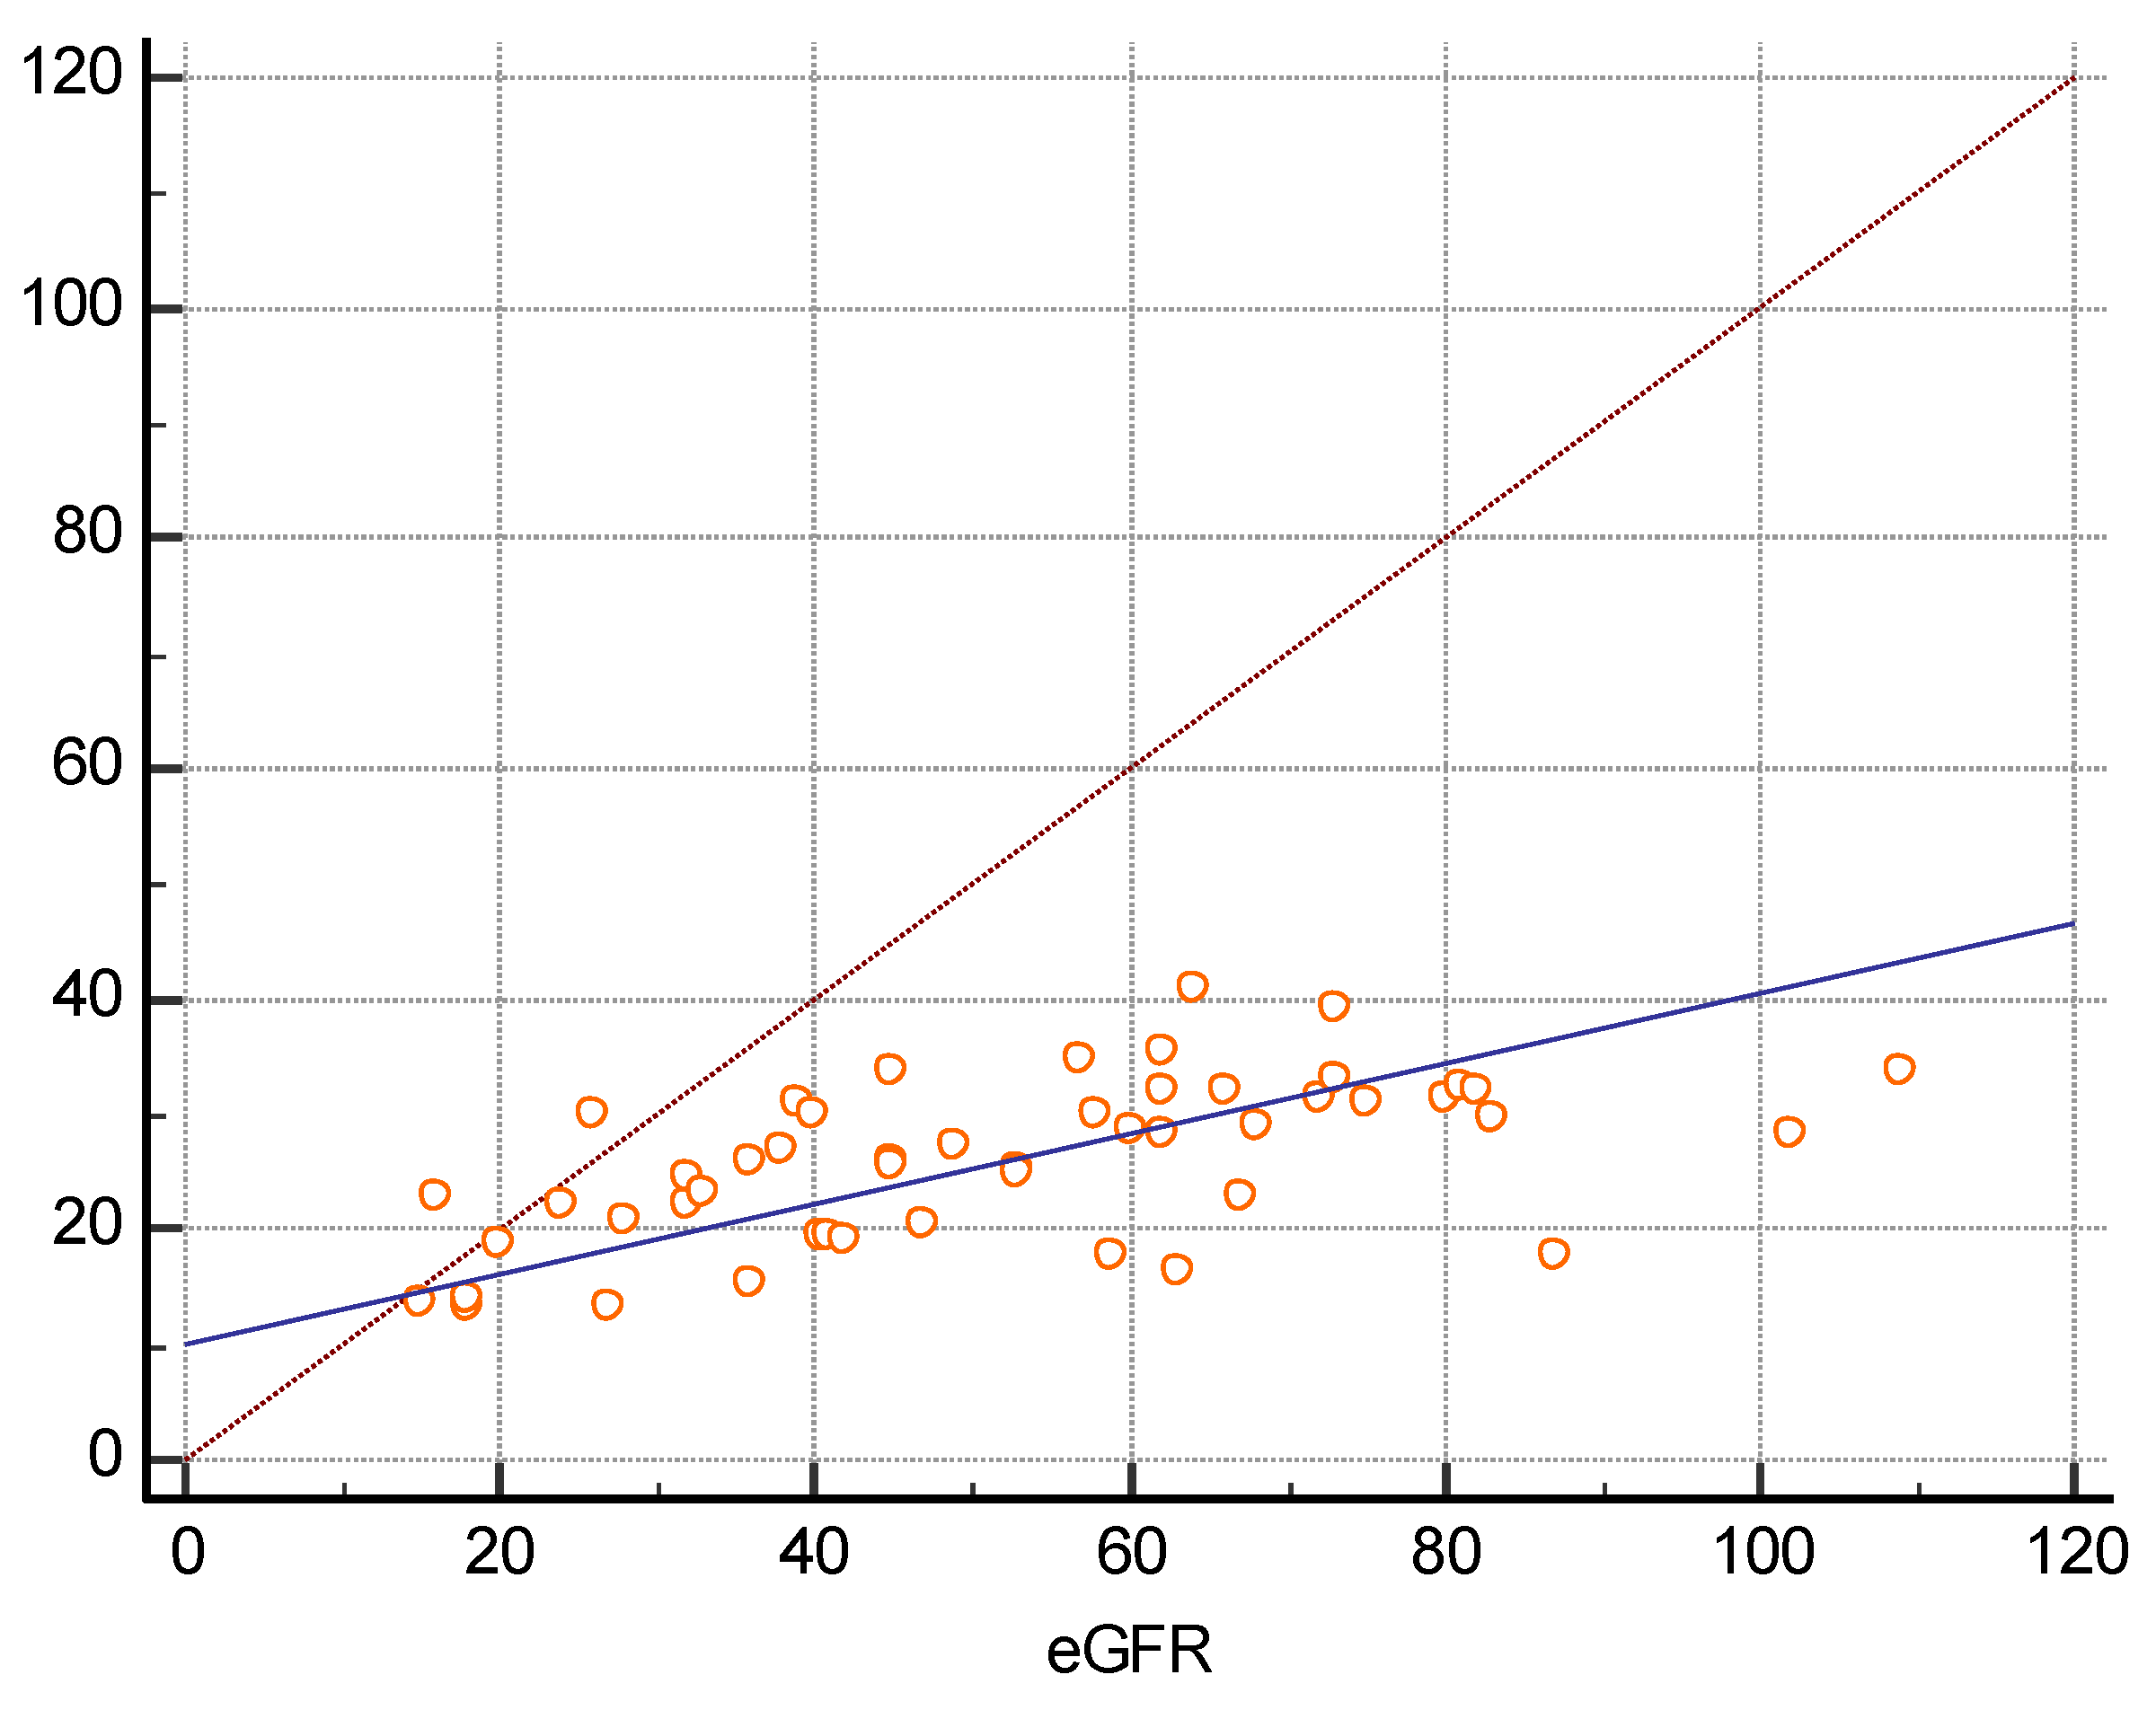

3. Results

| eGFR (mL/min/1.73m2) | 52 ± 22.6 | 0.5699 | p < 0.0001 |